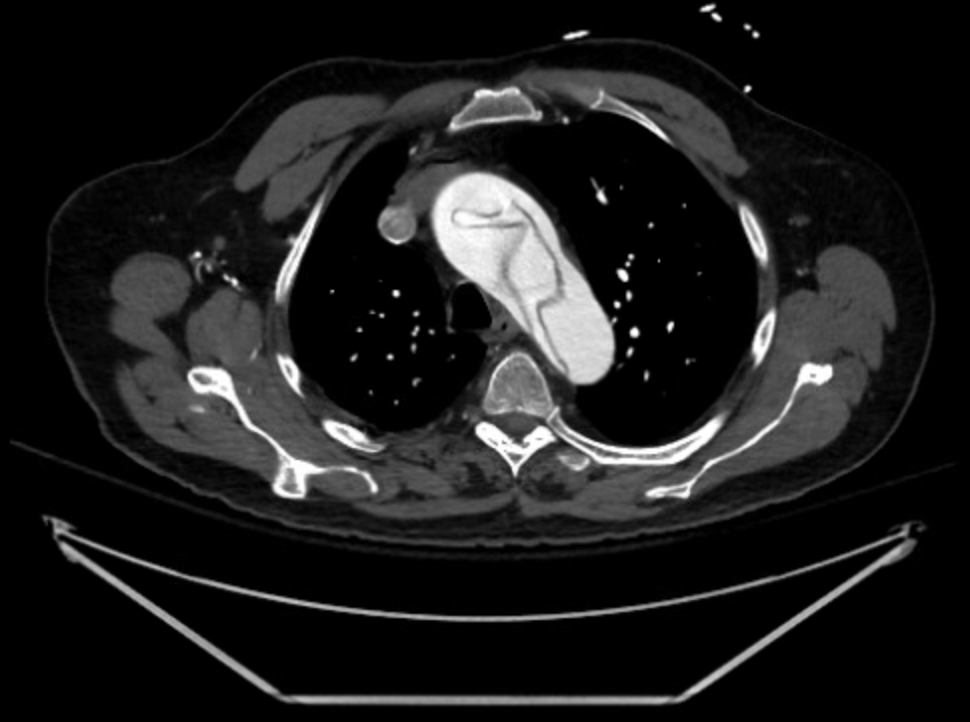

Based on these exam findings, an emergent CTA of the aorta was obtained, and demonstrated an extensive type A dissection involving the aortic valves, all 3 arch vessels, the right coronary artery, and the right common iliac artery with loss of signal at the right external and femoral arteries. The celiac, inferior mesenteric, and left renal arteries were all supplied by false lumens.

Figure 1: Transverse (left) and sagittal (right) sections of the patient’s initial computed tomography radiographic study, demonstrating a complex aortic dissection flap extending from the aortic valve through the iliac bifurcation.